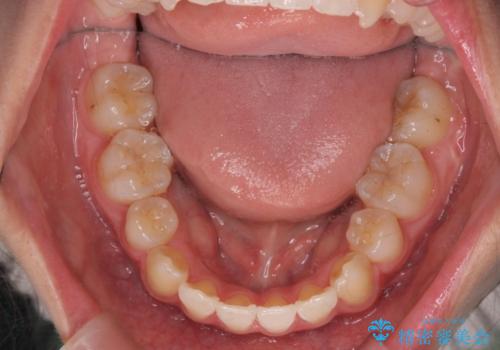

突き出た前歯を治したい 小臼歯抜歯+マルチブラケット矯正

- 突き出て、気になる前歯の角度の改善を求めて来院されました。

前歯の角度を改善するために小臼歯4本の抜歯を行いワイヤー マルチブラケットを用いて、しっかりと前歯の角度を改善する治療計画としました。